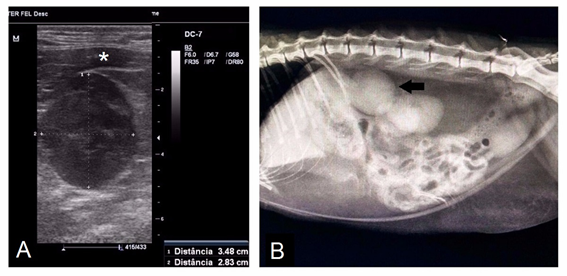

The cat was submitted to more detailed diagnostic study, with urinalysis and urine protein/creatinine ratio(PCR), test for feline immunodeficiency virus (FIV) and feline leukemia virus (FeLV), echocardiography and abdominal ultrasound. During the abdominal ultrasound and radiography (Figure 1A&B), an important increase in the left adrenal was identified, with approximate measurements of 2.5 x 3.1 cm in diameter, without invasion to adjacent structures and organs. The treatment consisted of fluid therapy and intravenous potassium replacement, as well as antihypertensive therapy with oral calcium channel blocker (Amlodipine 0.3 mg/kg every 12 hours). After normalization of serum levels and remission of clinical signs of hypokalemic polymyopathy and hypertension, the patient was discharged for conservative treatment at home with calcium channel blocker (Anlodipine 0.3 mg/ kg every 12 hours), potassium-sparing diuretic (Spironolactone 1 mg/kg every 12hours) and oral potassium citrate replacement (500 mg every 24 hours).

Figure 1 Diagnosis by adrenal mass imaging. A: Ultrasonographic image of the left adrenal gland, demonstrating a significant increase and closely linked to the V.cava caudalis (indicated by the asterisk). B: Abdominal radiography of the patient in lateral projection, the arrow indicates the adrenal gland.